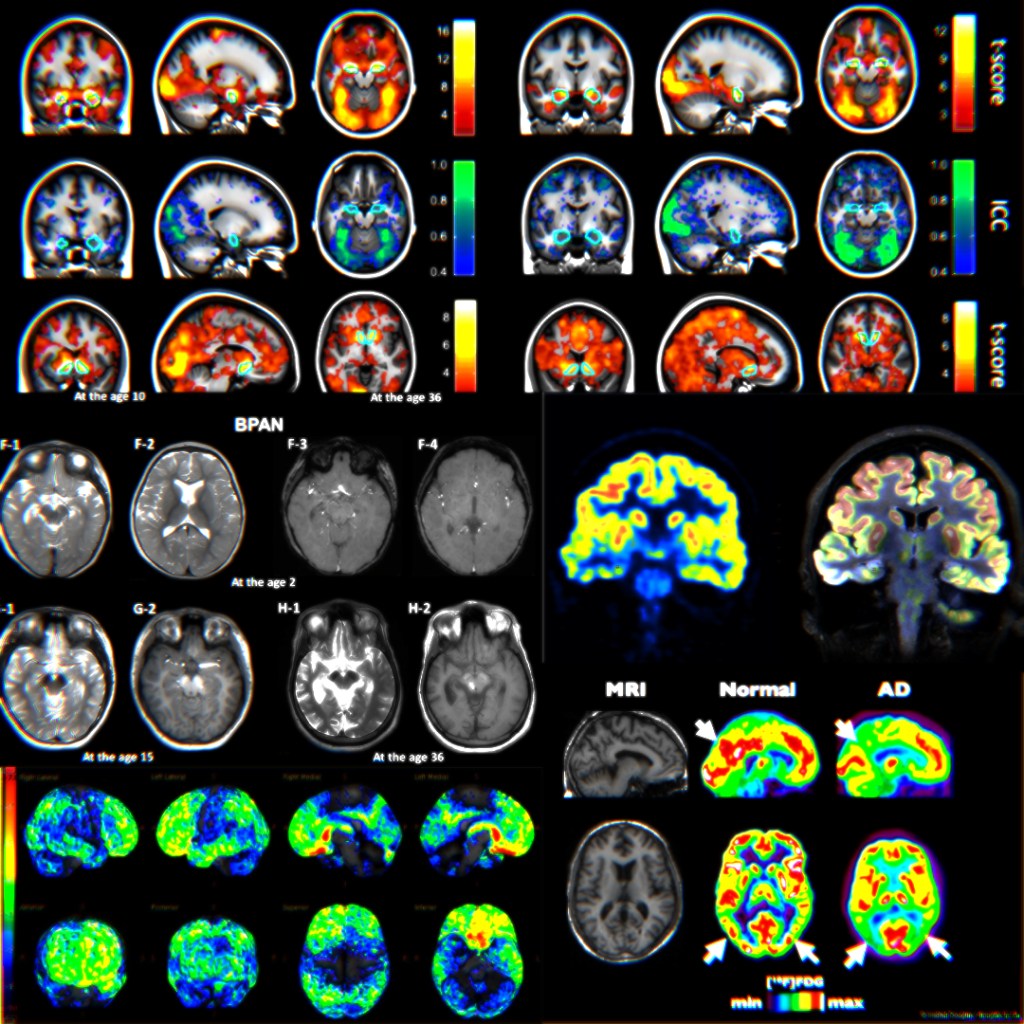

Here are some fMRI brain scans.

They could show the brain when shown a video of bullying. See how the colourful blobs light up? Red here, blue there, yellow scattered around here and there. The caption could say “Bullying causes an acute alarm state in the brain“.

It looks scientific. It looks important. But what does it actually tell you?

That brains do stuff when you see a video. Which, okay. Where else would the thinking happen? Your elbow?